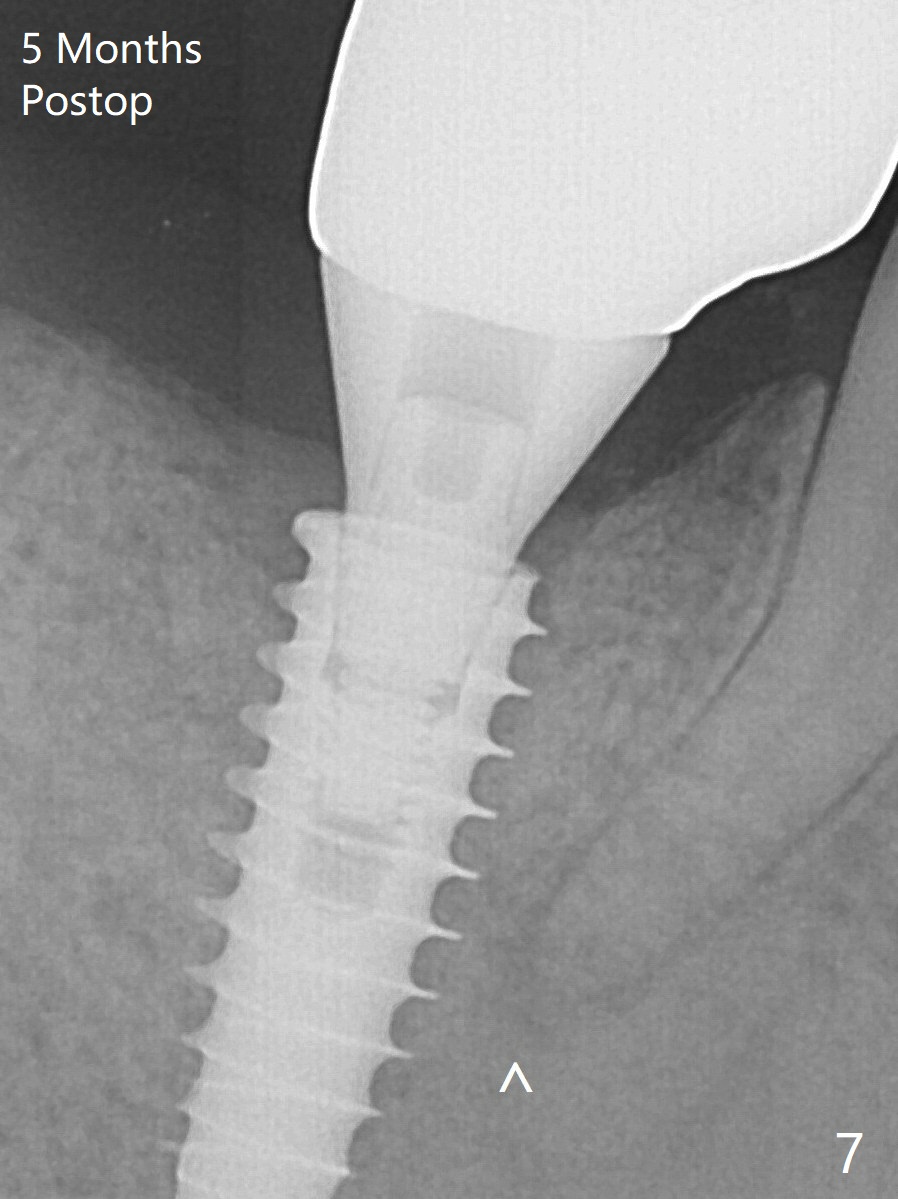

Bone graft seems to sink down and becomes denser 3 months postop (Fig.6 arrow).  The bone continues being denser 5 months postop (Fig.7).  There is periapical radiolucency of the tooth #29 (^).